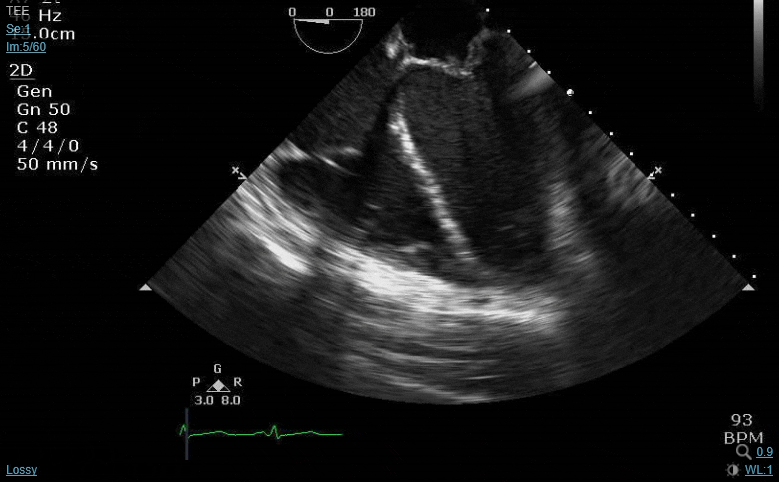

Patient is ESRD, TV endocarditis with pretty extensive vegetative burden in the R heart but no left sided veggies noted on pre-op TEE. Now coming to the OR for TV repair vs replacement.

On close examination, the AV looks like this:

Mild-mod AI coming from L-R commissure, AVA 1.7 by continuity equation. SAX of the AV is unexciting (no clear mobile echos seen), though my colleague acquired the images and the exam wasn’t as complete as I would have liked. I took over the case on CPB, so I didn’t have the opportunity to go back and interrogate the valve further (no 3D, etc).

Patient is fairly sick, R heart not doing great, so adding to the XC time would not be doing him any favors. That said, surgeon is fast and reasonable.

I’m curious, would anyone here advocate for opening the aorta to inspect this valve in light of positive blood cultures and known IE elsewhere in the heart? Or would you write this off as Lambl’s vs chunky calcium and move on? FWIW there were a few different ME AV LAX shots that displayed similar findings, so I did not get the sense that the finding in the above image was just a result of the imaging plan cutting through the sinus in an odd way (although as all of us know it’s very difficult to make that determination without the probe in your hands…)

I don't think it's Lambl's, but do you have a previous echo?

Valve leaflets thickened ratty and calcified, mobile echodensities, AI of unknown chronicity, and known endocarditis on the right side....I think you have to do an aortotomy and take a look at least.

These are just too suspicious:

That was my feeling as well- unfortunately my colleague hadn’t noted it or discussed with the surgeon, and he was already warming/getting ready to come off when I took over and pointed it out to him. He (the surgeon) felt it was probably calcium and opted to leave it alone, which was a fair decision in light of overall patient comorbidities and R heart issues (we struggled and kind of skimmed the treetops coming off, left the OR with a balloon pump; may not have made it off at all if bypass run was any longer).

I still felt like it was an awkward position to be in, trying to advocate for the patient without throwing my colleague who started the case under the bus. Curious how hard others with more experience would have pushed… At the end of the day I felt like I offered a recommendation as a consultant, which is all I can really do. Will be interesting to see the blood cultures clear, and if the follow up imaging shows anything on the AV (assuming patient survives long enough to have follow up imaging).

If you're already warming and he's a sick guy with a bad right heart then the ship has sailed at that point. Cause you have to think, what are the possible options if there are veggies on those calcified, ratty leaflets? A quick debridement/debulking without causing a perf or bad AI? Unlikely. So you're gonna re-pleg and extend the pump run long enough to do an AVR? Nahhhh.

Live to fight another day. Reculture. Abx if they're veggies. Pray they don't embolize somewhere bad as they heal.